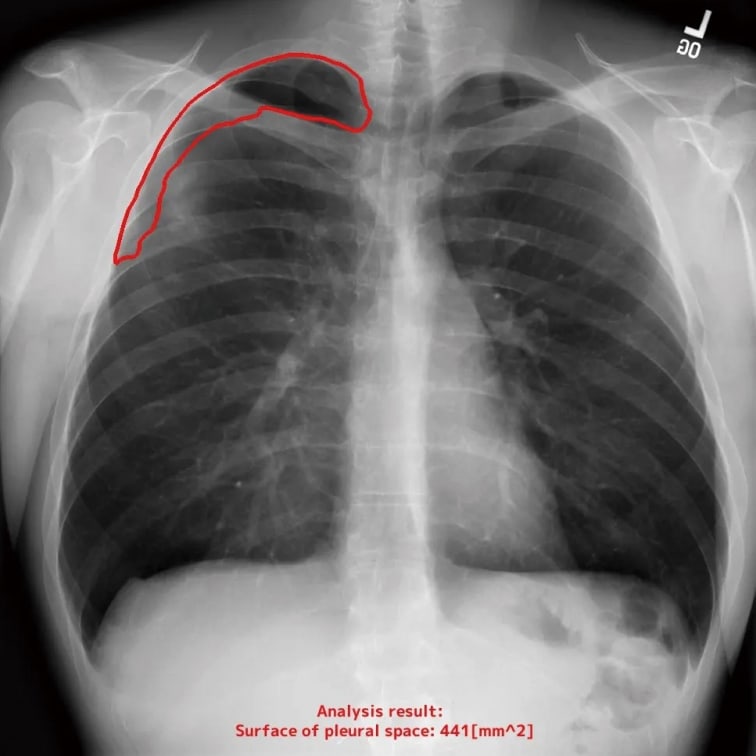

- 胸腔内の空気含有面積

自動計測機能